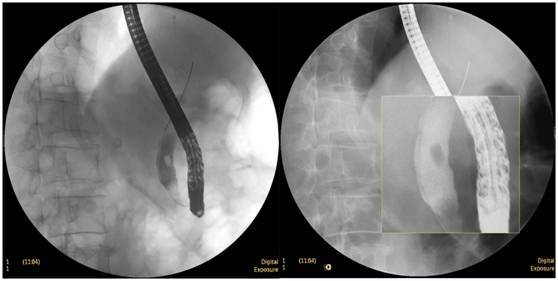

食管惡性腫瘤

食管癌并狹窄內(nèi)鏡下擴張支架植入術(shù),支架在脊柱背景下依然能清晰顯示。